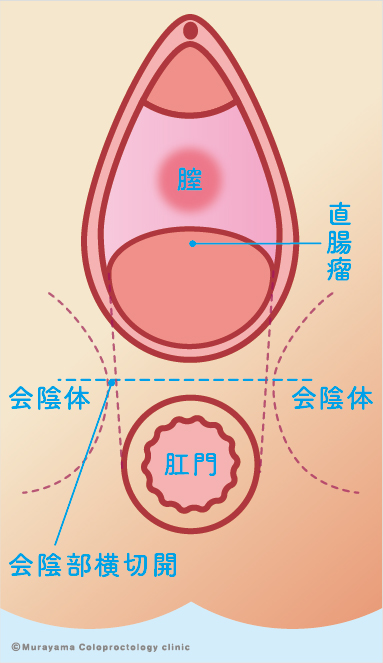

女性の肛門疾患 大阪市住吉区あびこ駅前の肛門外科 むらやま大腸肛門クリニック

女性の肛門疾患 大阪市住吉区あびこ駅前の肛門外科 むらやま大腸肛門クリニック

女性の肛門疾患 大阪市住吉区あびこ駅前の肛門外科 むらやま大腸肛門クリニック